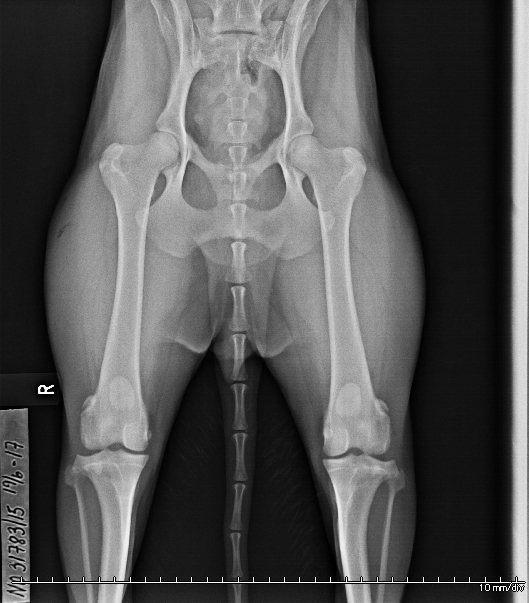

2 dogs had their hips x-rayed today

Today Snøfrost Skimrende Stjernelys, "Stjerne" and Snøfrost Ymer den digre Orca, "Orca", was hip x-rayed at Grenland Dyreklinikk.

The official result from NKK will take a few days, but the pictures looked good.

I always find it a bit scary to sedate the dogs, but it went well this time too. Stjerne and Orca seems to still feel some of the effects of the sedation, they are a bit tired and docile this evening. Tomorrow the sedation effect will have worne off, and everything will be back to normal

Orcas hofter / Orca's hips: